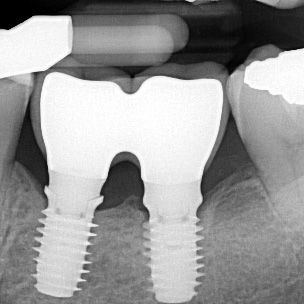

Soluciones para colocación y carga inmediata que ofrecen una estética superior.

El diseño cónico y el portafolio flexible respaldan las restauraciones inmediatas.

Planes de tratamiento personalizables para tratar las necesidades individuales de los pacientes.

Gestión simplificada del tejido blando para función y estética inmediatas.

Oseointegración confiable para sostener la función a largo plazo.